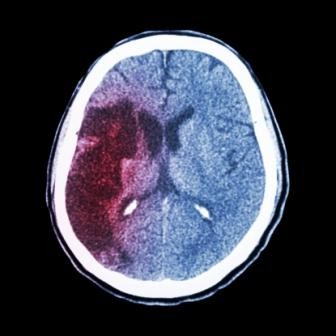

Gebruik van acetylsalicylzuur wordt aanbevolen na een transient ischemic attack (TIA) of een ischemische beroerte, omdat het blijkens trials de kans op een recidief met circa 13% reduceert. De herhalingskans is echter vooral in de eerste dagen met 10% erg hoog en observationele onderzoeken laten een veel groter effect van medicamenteuze behandeling in die periode zien dan gerapporteerd wordt door de langer lopende trials. Amerikaanse onderzoekers bedachten dat het effect van aspirine op de korte termijn wellicht wordt onderschat.

In de eerste 6 weken verminderde acetylsalicylzuur de kans op herhaling met circa 60% (HR 0,41; 95%-BI 0,30 tot 0,56). De kans op een ernstige beroerte was in deze periode zelfs 70% lager. Het grootste effect werd gezien bij patiënten die vanwege een TIA of een lichte beroerte waren geïncludeerd. Ook waren de beroertes die nog wel optraden gemiddeld minder ernstig. Enige verdere vermindering van de kans op een recidief werd in de tweede periode van 6 weken behaald. Na meer dan 12 weken was het effect van acetylsalicylzuur verdwenen.